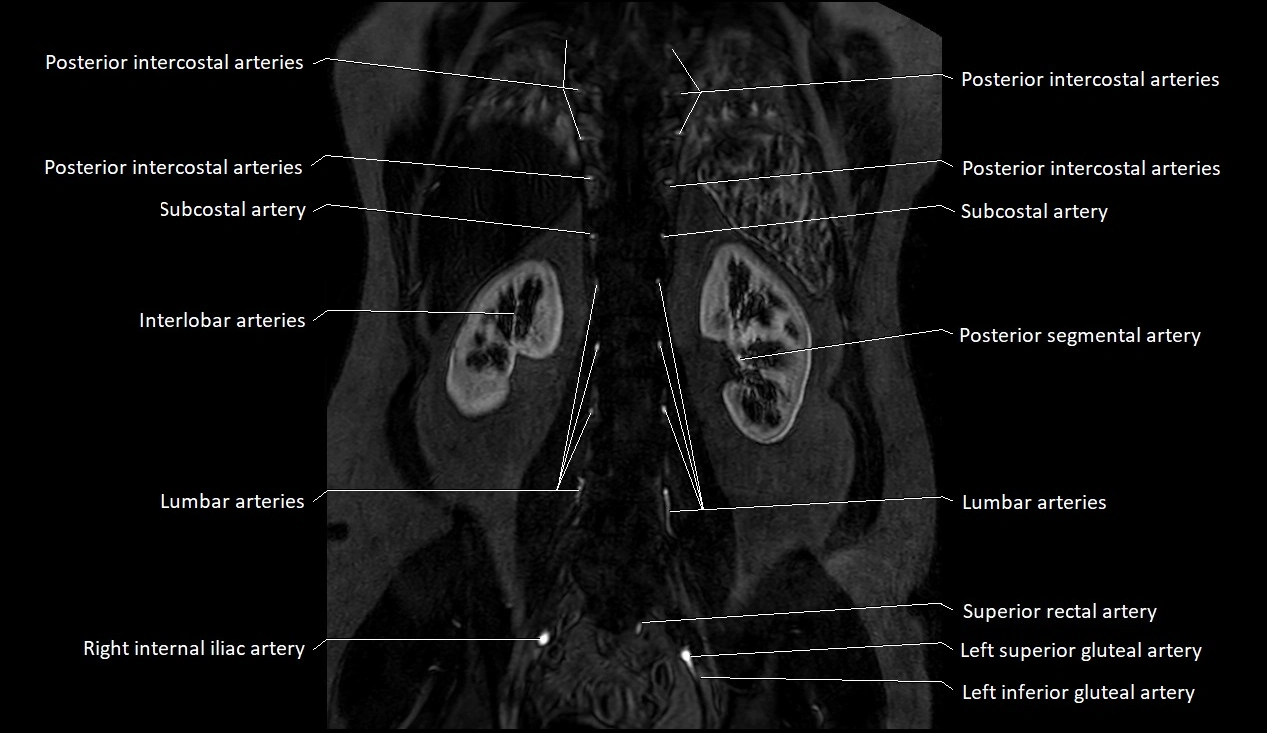

The abdominal aorta is the continuation of the thoracic aorta, beginning at the level of the aortic hiatus of the diaphragm (T12 vertebra) and terminating at the level of the L4 vertebra where it bifurcates into the right and left common iliac arteries. It lies slightly to the left of the midline and courses anterior to the vertebral bodies, surrounded by the retroperitoneal structures of the abdomen.

The abdominal aorta gives off numerous visceral and parietal branches, supplying the abdominal organs, pelvic structures, and lower limbs. It is the main conduit of oxygenated blood from the heart to the abdomen and lower body. The aorta is clinically significant as the common site of aneurysm, dissection, atherosclerosis, and traumatic injury.

Branches

• Paired visceral branches: middle suprarenal arteries, renal arteries, gonadal arteries (testicular or ovarian)

• Parietal branches: inferior phrenic arteries, lumbar arteries, median sacral artery

• Terminal branches: right and left common iliac arteries

MRA (Magnetic Resonance Angiography):

• Contrast-enhanced MRA provides high-resolution imaging of the aorta and its branches

• Allows 3D reconstruction of visceral, parietal, and terminal branches

• Excellent for evaluating aneurysm size, dissection flap, stenosis, or preoperative planning

• Non-invasive alternative to conventional angiography

CT images

image